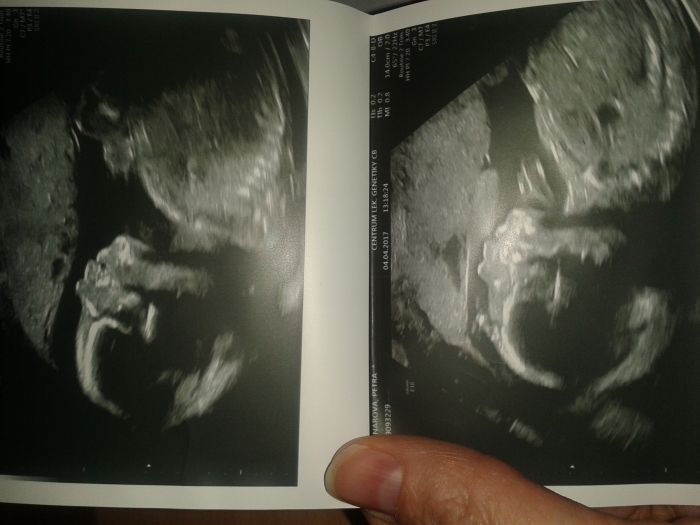

Ahoj holky, tak mam po velkem ultrazvuku ve II. trimestru. Pres muj vek mam pry vyborne vysledky a ani plodovku by nebrali :-). No bylo to krasne to nase srdicko videt. Pani doktorka uzasna....vse nam popsala a ukazala. Vzali nas na cas....no proste krasne odpolko. Jo a odpovida svemu stari.